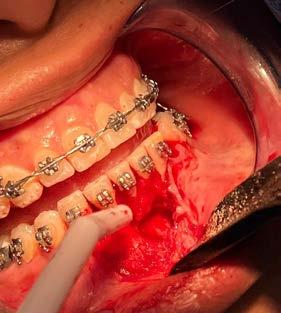

5 y 6. Alveolo tras la extracción atraumática del diente en posición 11, conservándose al máximo los tejidos duros y blandos para la colocación posterior del implante.

posible sobre los tejidos blandos y sobre el hueso remanente (Figura 5 y 6). Procedemos posteriormente a realizar una secuencia de fresado adaptada al lecho postextracción, alargando el alveolo con las fresas apicalmente y hacia palatino, donde se producirá el anclaje del implante. Con el lecho preparado colocamos el implante, quedándonos en vestibular el gap esperado de aproximadamente 4 mm como podemos ver en la

Figura 7. La utilización de un implante de longitud mayor y la inclinación hacia palatino nos permite lograr la estabilidad primaria necesaria para poder llevar a cabo una carga inmediata del implante. Una vez finalizada la inserción colocamos el transepitelial unitario para trabajar sobre el mismo generando la prótesis provisional de carga inmediata. Esta pieza intermedia (implante-prótesis) nos permite el uso de una interfase,

Figuras

que es altamente versátil y que nos da la posibilidad de generar restauraciones atornilladas o cementadas.25 La mayor ventaja que nos da el uso de las interfases, además de la versatilidad anteriormente mencionada, es que se eliminan gran parte de los fallos que pueden acumularse en la construcción de una prótesis provisional por los ciclos térmicos de cocción de la cerámica unida a la conexión de la corona con

el implante. En este caso, conexión con el implante (interfase) y corona se trabajan por separado y una vez finalizado el proceso de elaboración se cementan en frío.26-27

Una vez colocado el implante y el transepitelial para elaborar la prótesis de carga inmediata se realiza el sellado del gap vestibular, en este caso empleando únicamente PRGF-Endoret. El procedimiento es igual que

Figura 7. Imagen tras la colocación del implante ligeramente palatinizado con el gap situado en vestibular.

Figura 8. Imagen del implante colocado en el alveolo con el transepitelial unitario para llevar a cabo la carga inmediata.

Investigación clínica

9 y 10. Relleno del gap con PRGFEndoret, situando un coágulo recién activado de la fracción 2 en el fondo del alveolo y posteriormente un tapón de fibrina para la zona más superior (fracción 1 activada y retraída).

para el sellado de un alveolo postextracción, colocándose un coágulo de PRGF-Endoret recién activado de la fracción 2 (con alta liberación de factores de crecimiento) y sobre el mismo un tapón de fibrina autóloga sellando la zona más cercana al reborde alveolar (Figura 9 y 10). No se utilizan puntos de sutura para evitar el colapso del tejido blando del alveolo, además que por la adhesividad de la fibrina se mantiene en